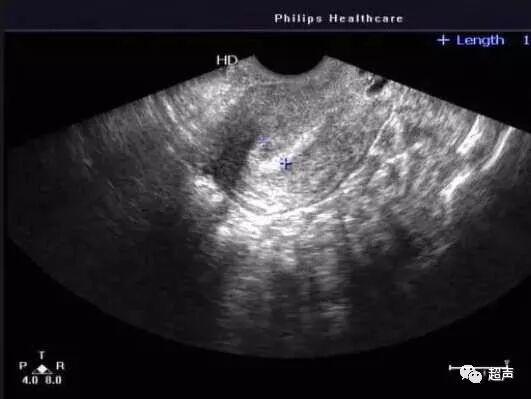

A型内膜常见于内膜增生早期(月经6-10日),此时内膜厚度一般为4-9mm,能明显看到宫腔内有三条线,即外层和中央为强回声线,外层和宫腔线间为低回声区。

A型内膜